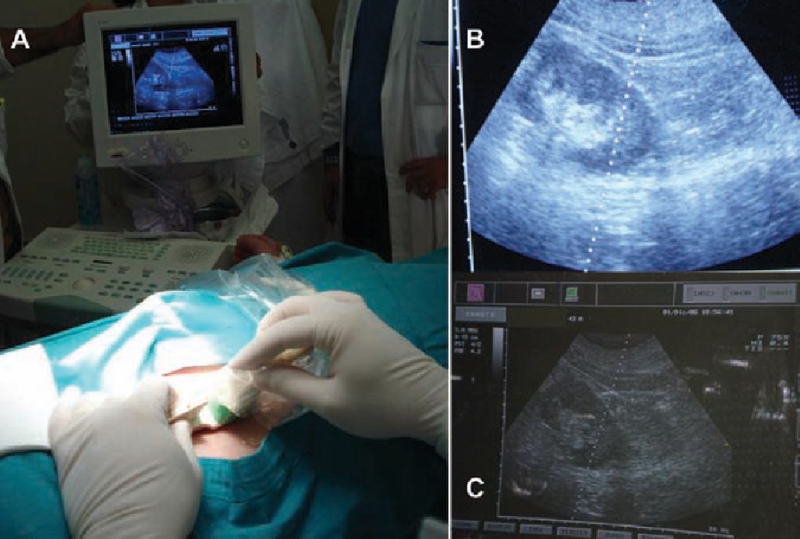

Sinh thiết thận dưới hướng dẫn siêu âm là một phương pháp xâm lấn tối thiểu giúp bác sĩ chẩn đoán các bệnh lý về thận một cách chính xác. Vậy sinh thiết thận dưới hướng dẫn siêu âm là gì? Quá trình thực hiện như thế nào? Hãy cùng Nhà thuốc Long Châu tìm hiểu qua bài viết dưới đây.

Do bệnh thận rất đa dạng, nguyên nhân và cơ chế bệnh sinh phức tạp nên biểu hiện lâm sàng của nhiều bệnh thận không hoàn toàn phù hợp với sự thay đổi mô học của thận. Vì vậy, sinh thiết thận dưới hướng dẫn siêu âm là một phương pháp thăm khám rất quan trọng và luôn được coi là tiêu chuẩn vàng. So với các phương pháp chọc dò truyền thống, sinh thiết thận dưới hướng dẫn siêu âm có ưu điểm là ít chấn thương hơn, ít đau hơn và tỷ lệ chọc đúng mẫu thành công cao hơn.

Tóm lại, sinh thiết thận dưới hướng dẫn siêu âm là phương pháp chính để chẩn đoán bệnh lý về thận. Nó sử dụng một kim đâm nhỏ xuyên qua da vào thận và lấy ra một lượng nhỏ mô thận để phân tích bệnh lý. Hiện nay, chủ yếu sử dụng sinh thiết thận dưới hướng dẫn siêu âm, phương pháp này ít gây chấn thương cho cơ thể con người và không gây tổn thương cho thận và các chức năng hệ thống trong hầu hết các trường hợp.